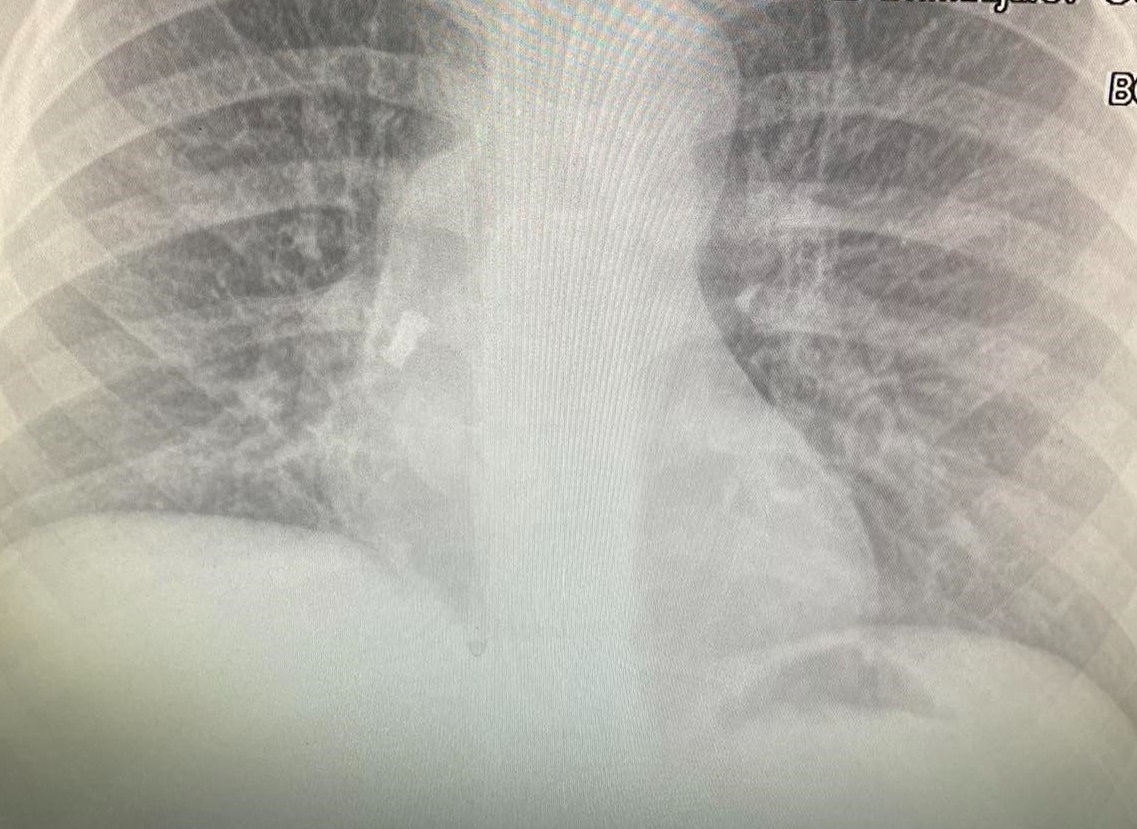

Л екари в Бургас спасиха дете със заседнал в трахеята млечен зъб. Петокласникът е прекарал 2 дни в реанимация, но вече е добре и е изписан за домашно лечение. Случаят е много рядък, тъй като момчето е живяло така близо две седмици. Майката е разказала, че зъбът е паднал по време на сън и детето го е глътнало. Родителите се усъмнили, че нещо не е наред, едва след като момчето започва да вдига температура. Лекували го с антибиотици, но тя не спадала. Личният лекар назначил рентгеново изследване и на снимката се видял зъбът. От него се е развила инфекция на дихателните пътища, което обяснява повишената температура.

Момчето е прието по спешност в отделението по УНГ в УМБАЛ Бургас. Операцията е извършена почти веднага от УНГ-специалистите доц. д-р Даниел Петков, д-р Ивайло Илиев и анестезиолога д-р Антон Григоров.

Операцията изисква майсторство и поставя на голямо изпитание целия екип. Дори специален инструмент трудно захваща хлъзгавия зъб. Още повече, че това се случва през тръбата, с която детето е интубирано и тя трябва да се извади и постави наново няколко пъти. Операцията травмира трахеята, гласните връзки и дихателните пътища, затова се налага престой в реанимация. Впоследствие от травматичните увреди се развива и пневмония, която вече е овладяна.